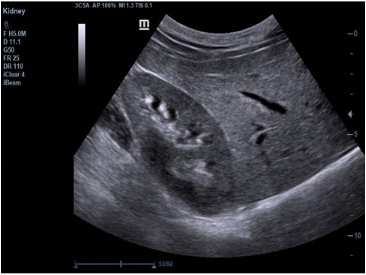

· 智能空间复合成像iBeam

多角度偏转图像复合,得到更佳的对比分辨率、更多的组织结构信息;

减少声影, 减少斑点噪声,使图像更加清晰。